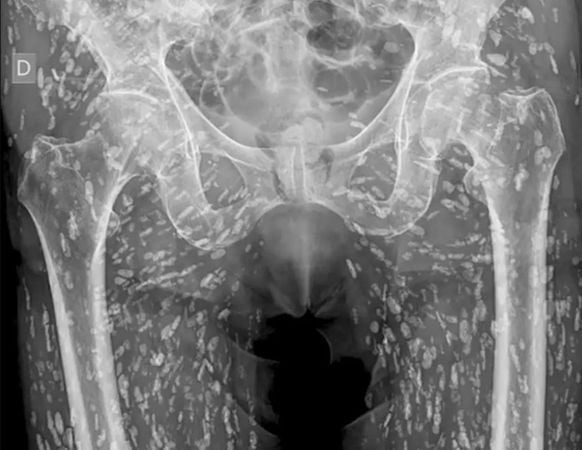

男子吃生猪肉屁股痛 骨盆X光长满诡异白点

(纽约23日综合电)一名男子因臀部疼痛而到医院检查,X光片显示,他的骨盆周围密密麻麻布满了数以百计的虫卵,被断定患上由猪肉绦虫(Taenia solium)引起的猪囊尾蚴病(Cysticercosis) ,而这种疾病是因为男子食用未煮熟或生猪肉所致。

《每日星报》报导,医疗专家卡利近日在X平台上传了这张X光片,声称这是他见过“最疯狂的X光片”,患者的骨盆周围散布著密密麻麻“已钙化的猪肉绦虫卵”。

他表示,这是一种食用未煮熟或生猪肉后所引起的疾病,猪肉绦虫的幼虫可散布全身,尤其容易出现在臀部、腿部的肌肉和软组织中。